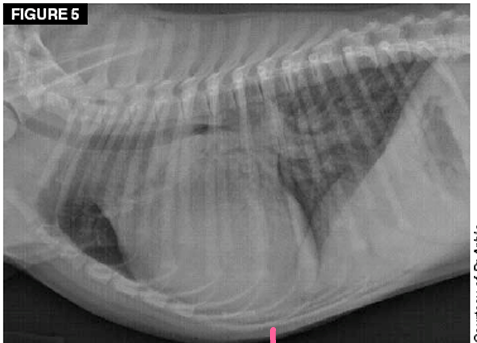

Total situs inversus

Heart is located towards the right side of thorax

Dextrocardia

Mirror image of the thoracic and abdominal organs

Situs inversus